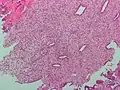

High magnification micrograph of decidualized endometrium due to exogenous progesterone (oral contraceptive pill). H&E stain

The endometrium consists of a single layer of columnar epithelium plus the stroma on which it rests. The stroma is a layer of connective tissue that varies in thickness according to hormonal influences. In the uterus, simple tubular glands reach from the endometrial surface through to the base of the stroma, which also carries a rich blood supply provided by the spiral arteries. In women of reproductive age, two layers of endometrium can be distinguished. These two layers occur only in the endometrium lining the cavity of the uterus, and not in the lining of the fallopian tubes.[4][5]

If there is inadequate stimulation of the lining, due to lack of hormones, the endometrium remains thin and inactive. In humans, this will result in amenorrhea, or the absence of a menstrual period. After menopause, the lining is often described as being atrophic. In contrast, endometrium that is chronically exposed to estrogens, but not to progesterone, may become hyperplastic. Long-term use of oral contraceptives with highly potent progestins can also induce endometrial atrophy.[13][14]